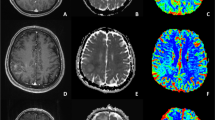

All study patients were initially diagnosed with glioma, 141 from the Cancer Genome Atlas and 131 from our tertiary institution, as training and validation sets, respectively. Images were analyzed by three neuroradiologists with 1–7 years of experience. MRI features including contrast enhancement pattern, necrosis, margin, edema, T2/FLAIR mismatch, internal cyst, and cerebral blood volume higher than normal cortex were reported using a structured reporting system. The pathology was stratified into five risk types: (1) oligodendroglioma, isocitrate dehydrogenase [IDH]-mutant, 1p19q co-deleted; (2) diffuse astrocytoma, IDH-mutant, grade II–III; (3) glioblastoma, IDH-mutant, grade IV; (4) diffuse astrocytoma, IDH-wild, grade II–III; and (5) glioblastoma, IDH-wild, grade IV. Significant predictors were selected using multivariate logistic regression, and diagnostic performance was tested using a validation set.

Reproducible imaging parameters exhibiting > 50% agreement across readers included the presence of necrosis, T2/FLAIR mismatch, internal cyst, and predominant contrast enhancement. In the validation set, prediction of risk type 5 exhibited the highest diagnostic performance with AUCs of 0.92 (reader 1) and 0.93 (reader 2) with predominant enhancement, followed by risk type 2 with AUCs of 0.95 and 0.95 with T2/FLAIR mismatch sign and no necrosis, and risk type 1 with AUCs of 0.84 and 0.83 with internal cyst or necrosis. Risk types 3 and 4 were difficult to visually predict.

Imaging parameters with high reproducibility enabling prediction of IDH-wild-type glioblastoma, IDH-mutant/1p19q co-deletion oligodendroglioma, and IDH-mutant diffuse astrocytoma were identified.

• Reproducible MRI parameters for determining molecular subtypes of glioma included the presence of necrosis, T2/FLAIR mismatch, internal cyst, and predominant contrast enhancement.

• IDH-wild type glioblastoma, IDH-mutant/1p19q co-deletion oligodendroglioma, and IDH-mutant low-grade astrocytoma were identified using MRI parameters with high inter-reader reproducibility.